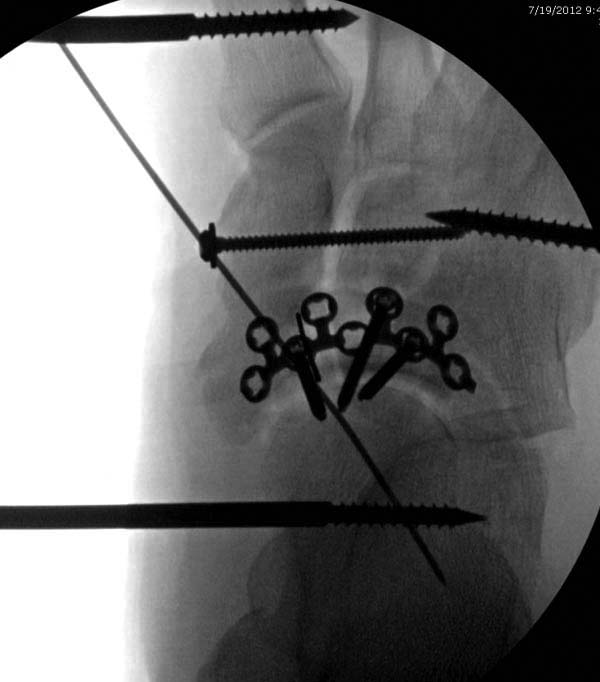

В нашем случае, травма в результате коллапса крыши. Открытый перелом. Ургентные Irrigation and Debridment, дистракция наружным фиксатором. В госпиталях первого уровня редко бывает изолированная травма, и на другой стороне повреждение стопы с переломом навикулярной кости. После обработки раны - вакуум и двухсторонние наружные фиксаторы.

Через три дня повторная I&D, где через рану манипулировали дистальным фрагментом с установкой пары межфрагментарных шурупов. На рану вакуум и следующая обработка закончилась закрытием раны. Отек держался немного дольше, чем обычно.